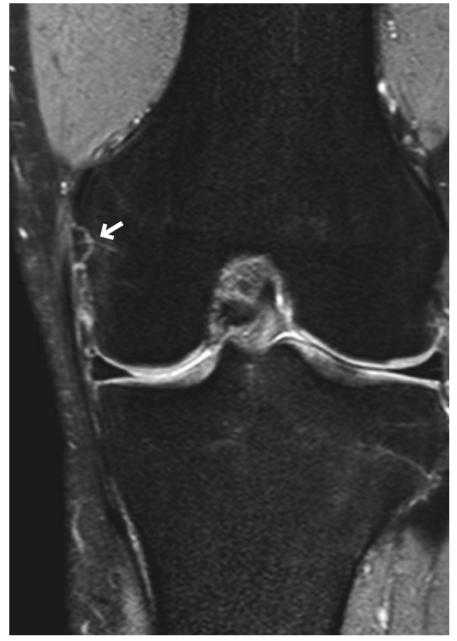

在1级MCL撕裂中,可以看到线性高信号,代表由于扭伤或劳损引起的韧带纤维水肿(图5.7)。然而,这种影像学发现也可以在内侧半月板撕裂和膝关节炎中发现。

图5.7的一级撕裂(拉伤)。一名20多岁的男子在演讲前一天滑雪受伤。冠状面FS PDWI显示沿MCL表层呈线性高信号,代表由于拉伤引起的水肿(箭头)